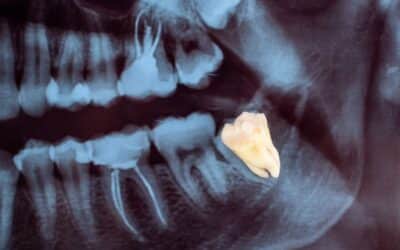

Do You Need a Bone Graft Before Getting Dental Implants?

Dental implants are a popular and effective way to replace missing teeth and restore your smile. But before getting implants, some...